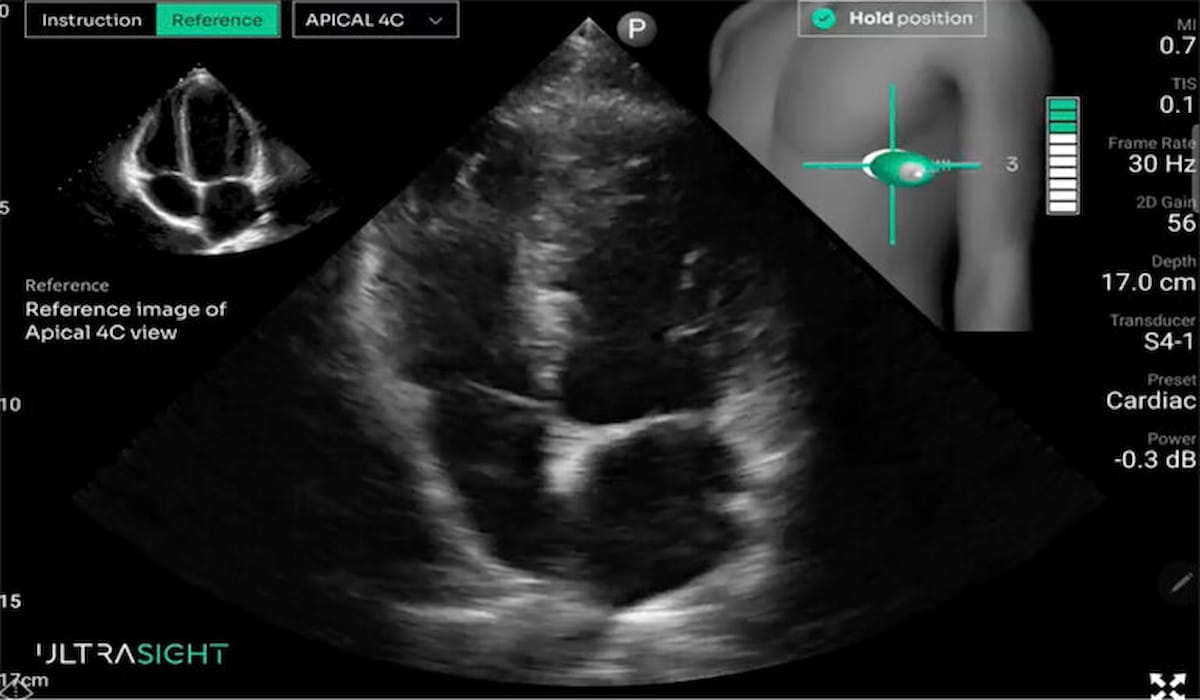

New research suggests that novice use of artificial intelligence (AI)-guided focused cardiac ultrasound (FOCUS) could significantly bolster the detection of reduced left ventricular ejection fraction (LVEF) or aortic valve stenosis (AS) beyond the capability of AI-enabled electrocardiography (AI-ECG).

In a new prospective study presented at the recent American College of Cardiology (ACC) conference, researchers assessed novice use of focused cardiac ultrasound (Lumify, Philips) guided by AI software (UltraSight) in 248 patients (median age of 63) who also had an AI-enabled electrocardiogram.

“The addition of AI-guided FOCUS acquired by novice scanners without imaging or clinical experience is a potential cost-effective method for screening populations at risk for structural heart disease,” noted lead study author Jordan Borgeson, M.D., who is affiliated with the Department of Cardiovascular Medicine at the Mayo Clinic in Rochester, Minn., and colleagues.

“Our research demonstrates that machine learning-guided ultrasound technology enables even novice users to accurately identify structural heart disease and early-stage heart failure,” said study co-author Jared G. Bird, M.D., a cardiologist at the Mayo Clinic. “Innovation in this space has the potential to significantly enhance early cardiovascular screening and make diagnostic imaging more accessible and cost-effective nationwide.”